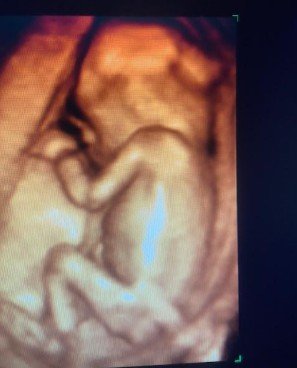

Control integral del embarazo

El control integral del embarazo garantiza un seguimiento cuidadoso de la salud de la madre y del desarrollo del bebé. En su consulta en Linares (Jaén), el Dr. Francisco Valdivieso Pérez supervisa cada etapa de la gestación con un enfoque cercano y siguiendo los protocolos de la Sociedad Española de Ginecología y Obstetricia (SEGO).

La atención incluye ecografías periódicas con tecnología 4D, ofreciendo imágenes y vídeo para que los futuros padres puedan ver la evolución del bebé con la máxima calidad. Estas exploraciones permiten valorar con detalle su crecimiento, posición y bienestar general.

Embrión a las 14 semanas